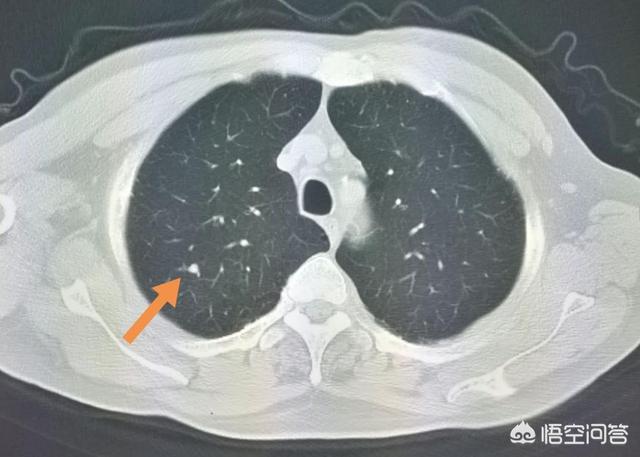

Der Pfeil zeigt auf den Knoten, der sehr klein war, als er im März 2016 entdeckt wurde, etwa 0,5 cm, und jetzt werden bei Routineuntersuchungen sehr viele Knoten wie dieser entdeckt.Es gibt keine Möglichkeit, auf den Bildern festzustellen, ob es gut- oder bösartig ist, sondern nur die Möglichkeit der Überprüfung, und die Überprüfung und Nachsorge ist auch das beste Mittel.

Sieben Monate später, bei der zweiten Nachuntersuchung im Oktober 2016, wurde deutlich, dass dieser Knoten größer und runder geworden war. Der vergrößerte Knoten bei der Nachuntersuchung sollte auf die Möglichkeit einer Bösartigkeit hinweisen, aber dieser Patient entschied sich dennoch nicht für eine Operation.